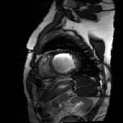

Medical data often exhibits long-tail distributions with heavy class imbalance, which naturally leads to difficulty in classifying the minority classes (i.e., boundary regions or rare objects). Recent work has significantly improved semi-supervised medical image segmentation in long-tailed scenarios by equipping them with unsupervised contrastive criteria. However, it remains unclear how well they will perform in the labeled portion of data where class distribution is also highly imbalanced. In this work, we present ACTION++, an improved contrastive learning framework with adaptive anatomical contrast for semi-supervised medical segmentation. Specifically, we propose an adaptive supervised contrastive loss, where we first compute the optimal locations of class centers uniformly distributed on the embedding space (i.e., off-line), and then perform online contrastive matching training by encouraging different class features to adaptively match these distinct and uniformly distributed class centers. Moreover, we argue that blindly adopting a constant temperature $\tau$ in the contrastive loss on long-tailed medical data is not optimal, and propose to use a dynamic $\tau$ via a simple cosine schedule to yield better separation between majority and minority classes. Empirically, we evaluate ACTION++ on ACDC and LA benchmarks and show that it achieves state-of-the-art across two semi-supervised settings. Theoretically, we analyze the performance of adaptive anatomical contrast and confirm its superiority in label efficiency.

翻译:医学数据经常呈现长尾分布和重度类别不平衡,这自然导致在对少数类别(即边界区域或罕见目标)进行分类时出现困难。最近的研究在长尾情况下通过装备医学影像的无监督对比标准,明显改进了半监督医学图像分割。然而,在标记的数据部分中,类别分布也极为不平衡,因此它们的表现如何仍不清楚。在本研究中,我们介绍一种采用自适应解剖对比度改进的对半监督医学分割行动的框架(ACTION++)。具体来说,我们提出了一种自适应监督对比损失,它首先在嵌入空间上计算出不同类别的优化位置(即离线),然后通过鼓励不同类别之间的特征与这些不同和均匀分布的类别中心相适应的在线对比匹配训练来进行自适应匹配。此外,我们认为,在长尾医疗数据中盲目采用常温度$\tau$不是最优的,因此通过一个简单的余弦计划来使用动态$\tau$来产生更好的多数类别和少数类别之间的分离。在实证方面,我们在ACDC和LA基准测试中评估ACTION++,并展示了其在两种半监督设置下的最新成果。从理论上讲,我们分析了自适应解剖对比度的性能,并证实了它在标签效率上的优越性。